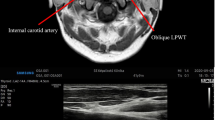

In patients with OSA there is the narrowing or blocking of the upper respiratory tract from the oropharynx to the hypopharynx during sleep, resulting in ineffective or absent breathing. Accurate understanding of the upper respiratory tract anatomy is the key to screening for OSA. The Starling resistor model has been proposed to explain the complex series of events that occur in patients with OSA during sleep (Fig. 2) [24]. Pharyngeal size, compliance, and the dynamic behavior of the upper airway have been considered important factors in the pathogenesis of OSA. So, the assessment of the precise narrowing site of the upper airway may not be only one of the keys in understanding the pathogenesis of this disorder but also in improving the management of this condition. APh has the potential to be a useful tool for localizing the possible site(s) of upper airway obstruction in cases of OSA.

Starling resistor model [24]

In 1984, Rilive et al. [33] first applied APh to patients with OSA. By measuring the upper respiratory tract morphology, it was concluded that the average cross-sectional area of the pharyngeal cavity and the average glottal cross-sectional area in OSA was smaller than in patients without OSA. Kamal et al. [15] used special techniques during the examination to locate the oropharyngeal junction and the glottis to generate a mapped acoustic throat map, calculating the minimum pharyngeal area and glottal area. The studies’ results showed that the APh can accurately determine the pharyngeal obstruction [14], and had been validated by computerized axial tomography (CT) [34] and magnetic resonance imaging (MRI) [35].